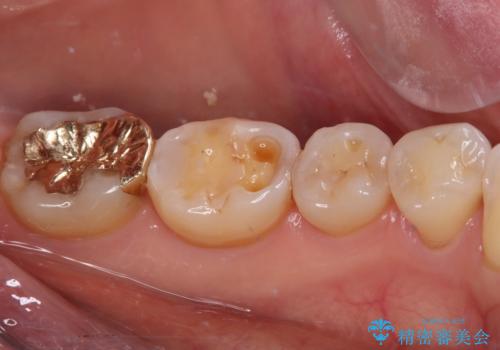

- 奥歯の銀歯をすべてゴールドにすることを希望された患者様です。

セラミックインレーによる補綴治療も提案しましたが、ご自身で強い咬合力を認識しており、歯にもインレーにもダメージの少ないゴールドインレーにて処置することとしました。